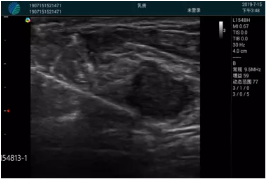

腺體內(nèi)部清晰顯示一低回聲塊影,形態(tài)不規(guī)則,邊界模糊,邊緣呈毛刺狀,內(nèi)部見砂礫樣鈣化

M20引導下穿刺活檢術(shù)

M20引導下平面內(nèi)穿刺取出的腫塊組織